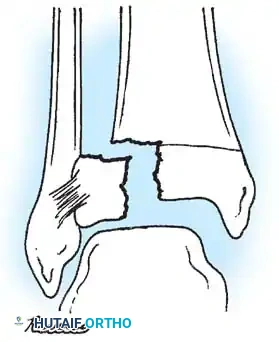

Fig. 33-173: Salter-Harris type I and II fractures with posterior displacement of the tibial shaft may severely injure the popliteal artery.

Wozasek et al. reported that 13% of patients with proximal tibial physeal injuries exhibited peripheral ischemia. Immediate vascular assessment (Ankle-Brachial Index, Doppler ultrasound, or CT angiography) is mandatory for any displaced proximal tibial fracture.

- Type I and II Fractures: Most can be managed with closed reduction and a bent-knee cast. However, posterior displacement requires meticulous reduction to relieve arterial tension. Unacceptable angulation must be corrected; malunion in older children will not remodel sufficiently.

- Type III Fractures: These present in two distinct patterns:

- An intra-articular fracture analogous to an adult tibial plateau fracture.

- A fracture propagating through the tibial tuberosity physis, extending proximally across the epiphysis and into the knee joint.

Fig. 33-174: Salter-Harris type III fracture of the proximal tibia. A, Fracture analogous to a tibial plateau fracture. B, Fracture through the tibial tuberosity and across the epiphysis into the knee joint.

These tuberosity-extending fractures are not simple avulsions; they are massive, tongue-type Salter-Harris III injuries that lift the entire tibial tuberosity and anterior proximal physis superiorly. They almost universally necessitate open reduction and internal fixation (ORIF) to restore joint congruity and extensor mechanism continuity.